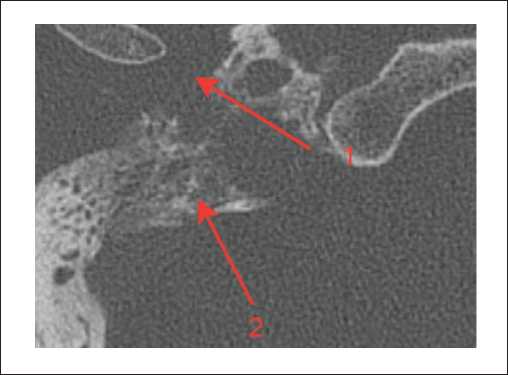

Пациенты третьей группы с диагностированной распространенной параганглиомой предъявляли жалобы на отсутствие слуха с пораженной стороны, периодическое онемение лица, периодические эпизоды кровотечения из слухового прохода. У 6 пациентов, которые до поступления в нашу клинику неоднократно подвергались хирургическим вмешательствам, отмечался парез лицевого нерва со стороны поражения, который соответствовал 5–6 степени по шкале House – Brackmann. При отоскопии у пациентов определялось выпирающее в просвет наружного слухового прохода красно-бордовое пульсирующее объемное образование. По данным лучевых исследований, на КТ височных костей у пациентов определялся мягкотканный субстрат, заполняющий барабанную полость. Крыша барабанной полости была истончена, местами не определялась (1). Костная стенка канала внутренней сонной артерии не прослеживалась. На уровне луковицы яремной вены определялось мягкотканное образование, которое разрушало костные стенки гипотимпанума (2) (рисунок 5).

Рисунок 5. КТ правой височной кости, аксиальная проекция. Параганглиома, тип С: задняя стенка нижнечелюстной ямки местами не определяется (1). На уровне яремной ямки определяется мягкотканное содержимое, которое разрушает костные стенки гипотимпанума (2).

На МРТ головного мозга и мягких тканей шеи определялось распространение образования на капсулу улитки и на область правой мостомозжечковой цистерны (рисунки 6, 8, 9). Соответствующие отделы головного мозга не изменены. Определялись признаки распространения процесса по ходу внутренней яремной вены (1). Просвет внутренней яремной вены в этой области не прослеживался (2) (рисунок 7).